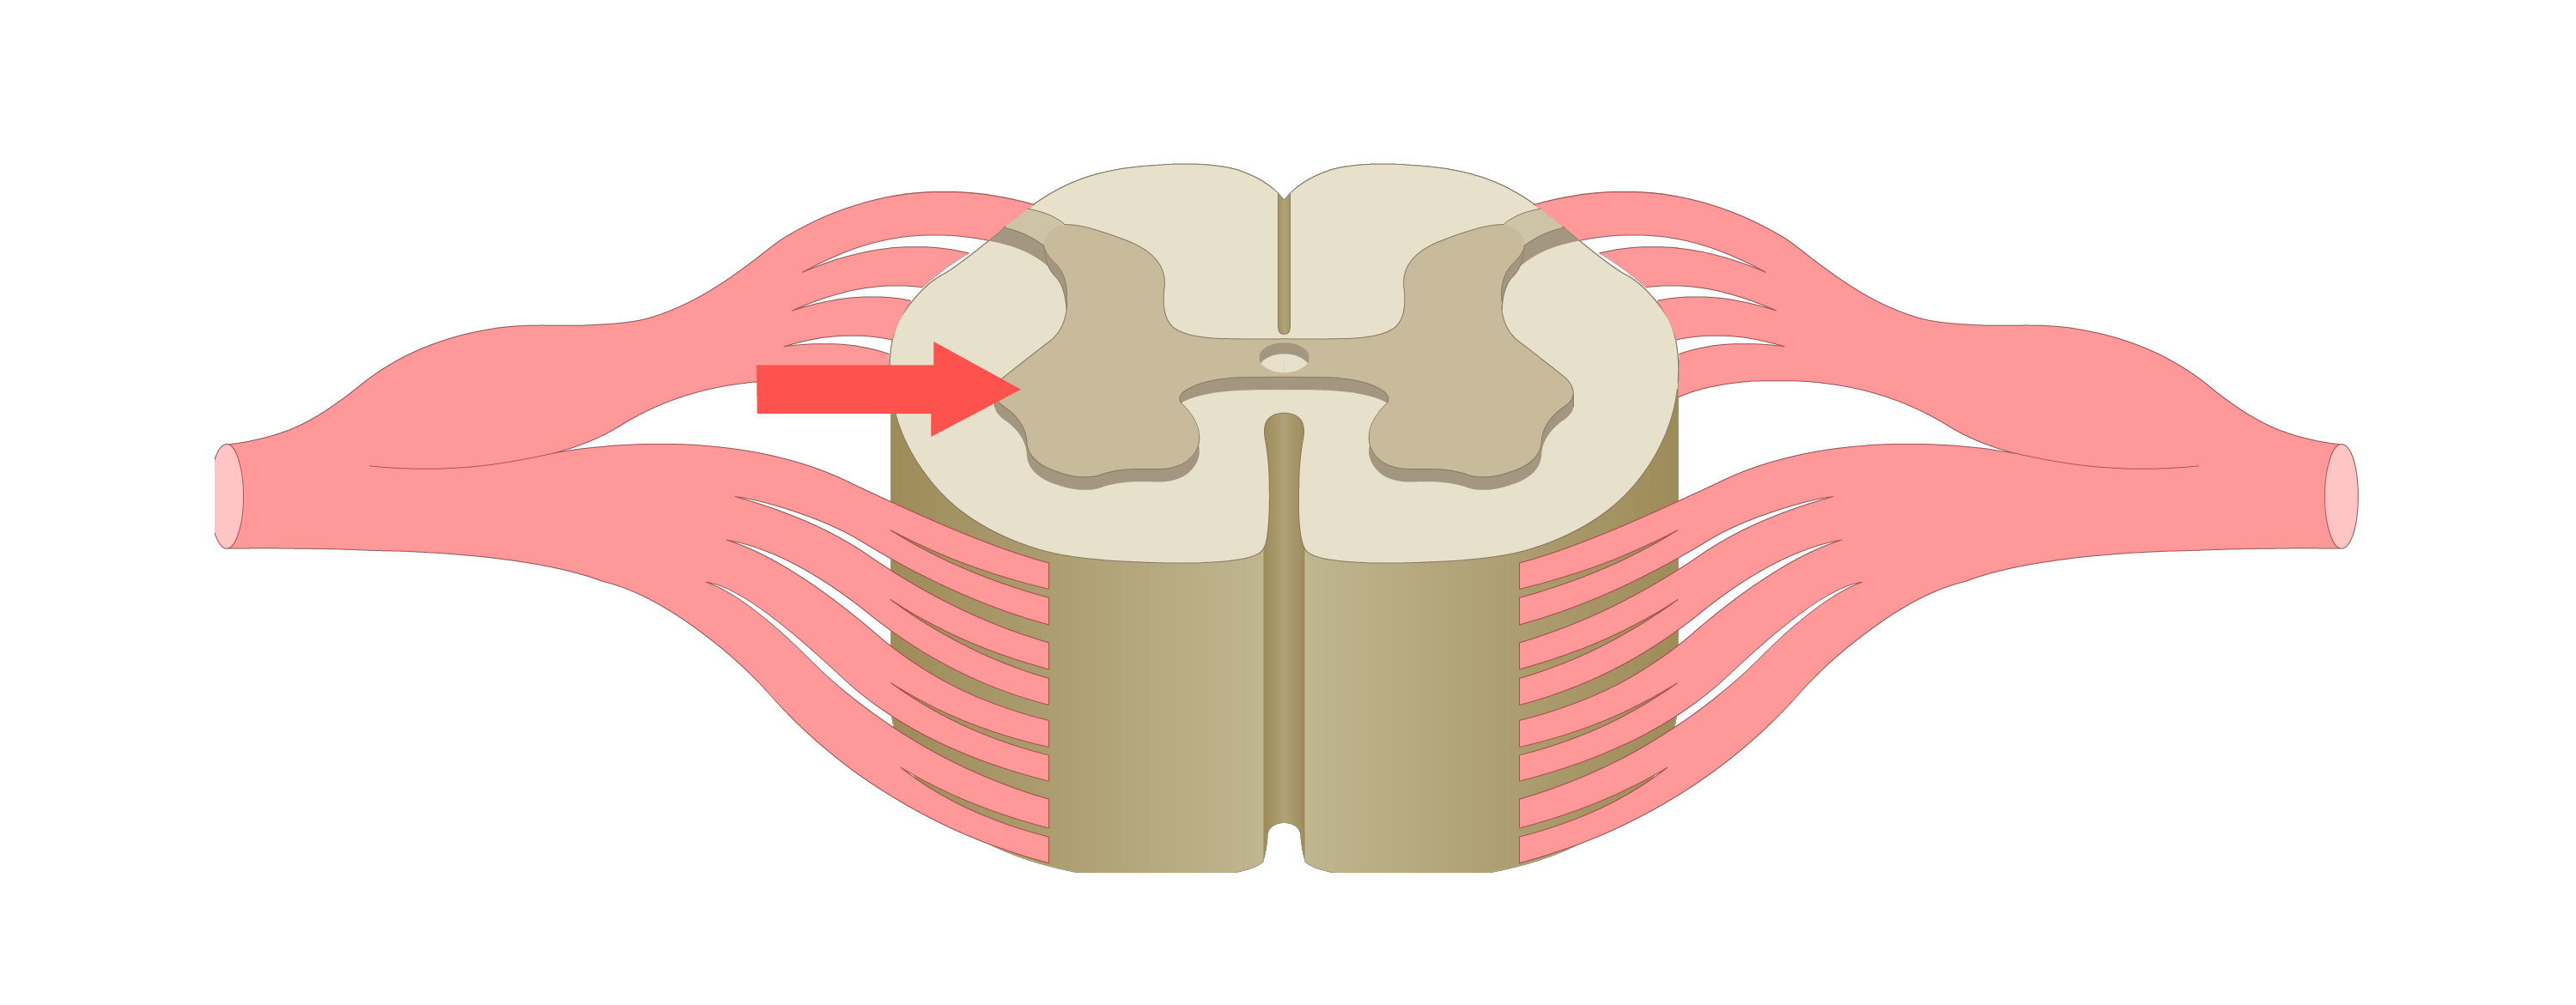

motor tracts

sensory tracts

efferent neuron

carries motor action potentials from integration center to effector organ

control/integration center

single/multiple synapses bw sensory & motor neurons; always in CNS